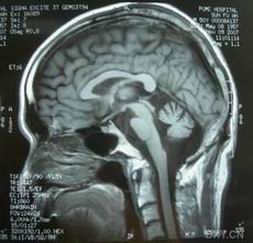

(3)CT檢查可見雙側殼核低密度灶。MCI顯示殼核、蒼白球T2低信號,提示鐵沉著,早期病例可與Parkinson病區別。PET可顯示殼核和尾狀核18F-6-fluorodopar和11C-nomifensin攝取較正常減低,而Parkinson病這兩種顯像相對正常。

1,MR是最有價值的診斷方法,T2加權像顯示豆狀核低密度,紅核與黑質間正常存在的高信號降低,並顯示鐵沉積增加由於膠質細胞、膠質纖維增生及毛細血管增多使病變組織含水量增多,延長Tl、T2值,在Tl加權像呈低信號,T2加權像呈高信號。

O’Brien報告1例SND患者MRI顯示殼核信號減少,尤其是在後外側T2加權圖像低於蒼白球水平此外殼核明顯縮小,中腦由於黑質網狀部和紅核信號減小而顯示不清,作者認為SND的症狀似乎由於特殊結構功能的聯繫,殼萎縮與肌強直和對藥物不敏感有關肌強直的嚴重程度和殼信號減少程度密切相關。戴啟麟報導6例SND患者MRI檢查均異常。2例雙側外囊區對稱出現白質退行性變4例出現雙側殼核不規則T1W1低信號,T2W1高信號其中1例同時伴腦幹小腦萎縮,而6例CT檢查均正常。